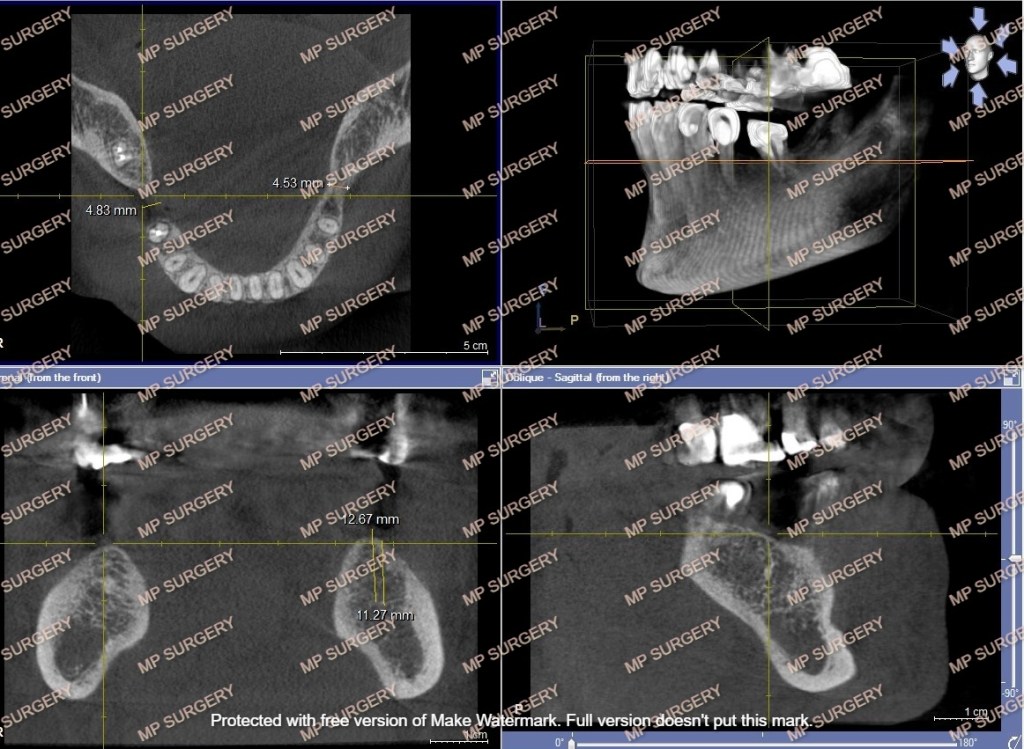

1. Λεπτομερής προεγχειρητική μελέτη που περιλαμβάνει έλεγχο τόσο της περιοχής της επέμβασης ενδοστοματικά, όσο και το γενικό ιατρικό ιστορικό. Ελέγχονται η στοματική υγιεινή, τα δόντια μπροστά και πίσω από τη νωδή περιοχή, τα δόντια της αντίθετης γνάθου, η υφή και το πάχος των ούλων, η ποιότητα και ποσότητα του υπάρχοντος οστού, με πανοραμική και τομογραφία (οδοντιατρική αξονική ή CBCT). Κακή στοματική υγιεινή, φλεγμονή του οστού ή των παρακείμενων δοντιών, ουλίτιδα, έλλειψη χώρου σε κάθετο ή οριζόντιο επίπεδο, ανεπαρκές οστό αποτελούν αντένδειξη για τοποθέτηση εμφυτευμάτων. Ένα εμφύτευμα δεν τοποθετείται σε οστό που φλεγμαίνει ή δίπλα σε δόντια με φλεγμονή γύρω από τη ρίζα τους γιατί υπάρχει κίνδυνος να επεκταθεί η φλεγμονή στο εμφύτευμα, να μολυνθεί αυτό και να μην ενσωματωθεί ή να απωλεστεί. Στην προεγχειρητική τομογραφία της νωδής περιοχής γίνονται μετρήσεις του οστού στις 3 διαστάσεις, βάσει των οποίων αποφασίζεται ο αριθμός και οι διαστάσεις των εμφυτευμάτων που θα τοποθετηθούν. Τα τελευταία χρόνια χρησιμοποιούνται ειδικοί νάρθηκες με οπές που καθοδηγούν την ακριβή τοποθέτηση των εμφυτευμάτων. Σχετικά με το γενικό ιατρικό ιστορικό, λαμβάνονται υπόψη, μεταξύ άλλων, καρδιολογικά νοσήματα, ανοσοανεπάρκειες, αυτοάνοσα νοσήματα, ρευματοπάθειες, οστεοπόρωση, συστηματική φαρμακευτική αγωγή και αρρύθμιστος σακχαρώδης διαβήτης.